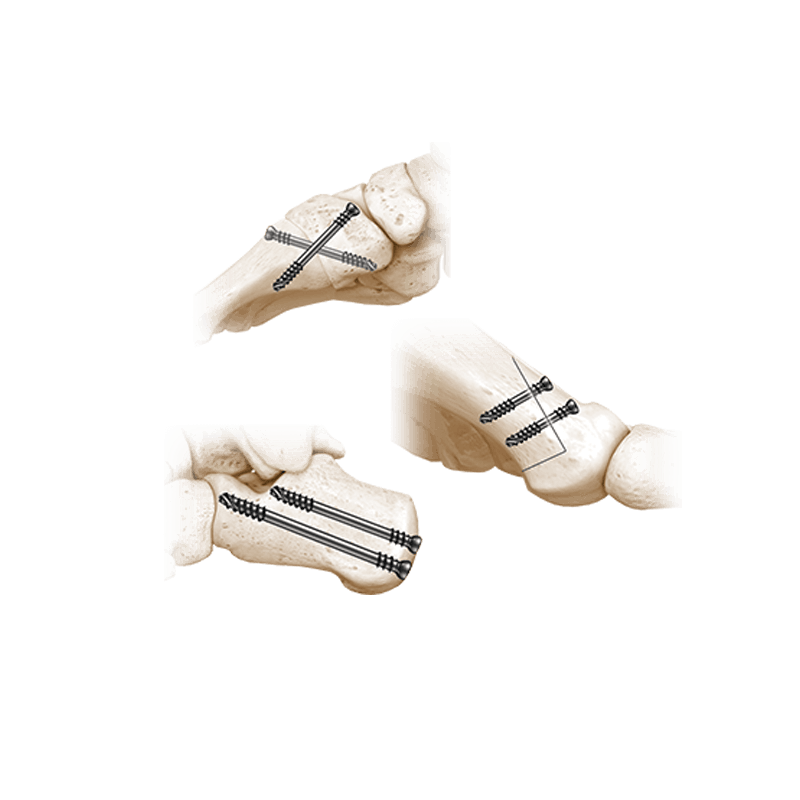

Fixation Devices - Compression Hardware

IBS™-B Beveled Screw System

IBS™-B Beveled Screw System delivers the strength, control, and versatility your MIS workflow demands.

NeoSys® Single-Use Instrumentation

Providing precision, efficiency, and convenience during surgery

NeoSpan® SE Compression Staples

A superelastic compression-ready fixation system designed for fixation of fractures, fusions, or osteotomies